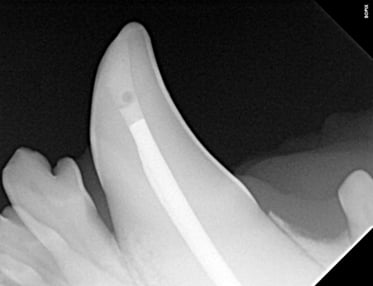

Below: Radiograph finding working length

%20Case%202%20-%20July%202024/Working%20length%20radiograph%20during%20RCT.jpg?width=373&height=287&name=Working%20length%20radiograph%20during%20RCT.jpg)

Upon reaching the pulp chamber, a radiograph was captured to verify cleaning at the designated working length, determined to be 42mm in this case.